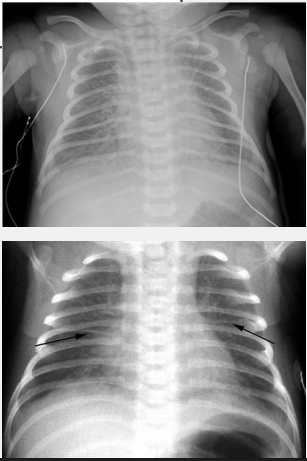

perihilar streaking, fluid, self limited, oxygen

Transient Tachypnea of the Newborn: Diagnosis and Treatment

-CXR → central vascular markings (________ ___________) and ______ in lung fissures

-Treatment → _____ ________ (resolves within 12-48 hours), may need nCPAP and/or __________